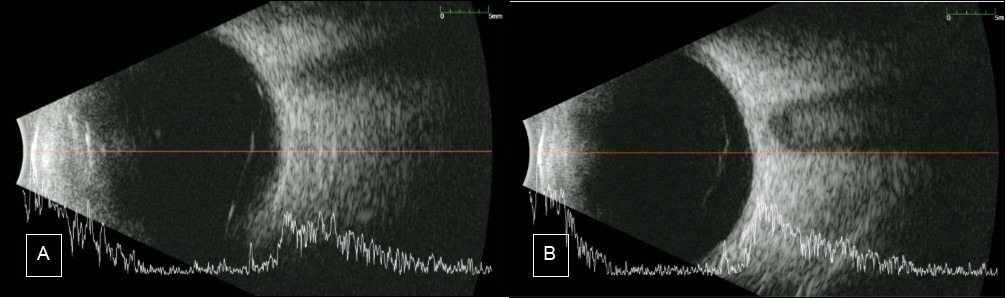

Figure 5.B-scan A) Case 1 Right eye: shows an almost complete PVD with remaining attachment to the optic nerve. B) Case 2 Right eye shows complete PVD

Going back to our patients, around 50% of the retina is still visible and the hemorrhage was confined at the posterior vitreous cavity near the retina. Ocular ultrasound (B-scan) was done to the 2 patients’ affected eye and both showed liquified vitreous. For the first case, posterior vitreous detachment (PVD) was almost complete, the only remaining attachment is to the optic disc. On the other hand, there was a complete PVD for the second case. (see Figure 5). The status of PVD in our patient means that there is less scaffold for neovascular tufts and preretinal membranes to develop. Both patients also underwent PRP. ‘The main goal of PRP is the destruction of retinal cells in the areas of hypoxia, especially muller cells which are responsible for upregulation of VEGF. Another therapeutic effect of PRP is the induction of PVD. Studies have shown (Sebag, 1990 cited by Kroll7) higher incidence of PVD following PRP. Progression of PVD can be observed 3-6 months following PRP’7 Thus, PRP might have promoted PVD in our patients.